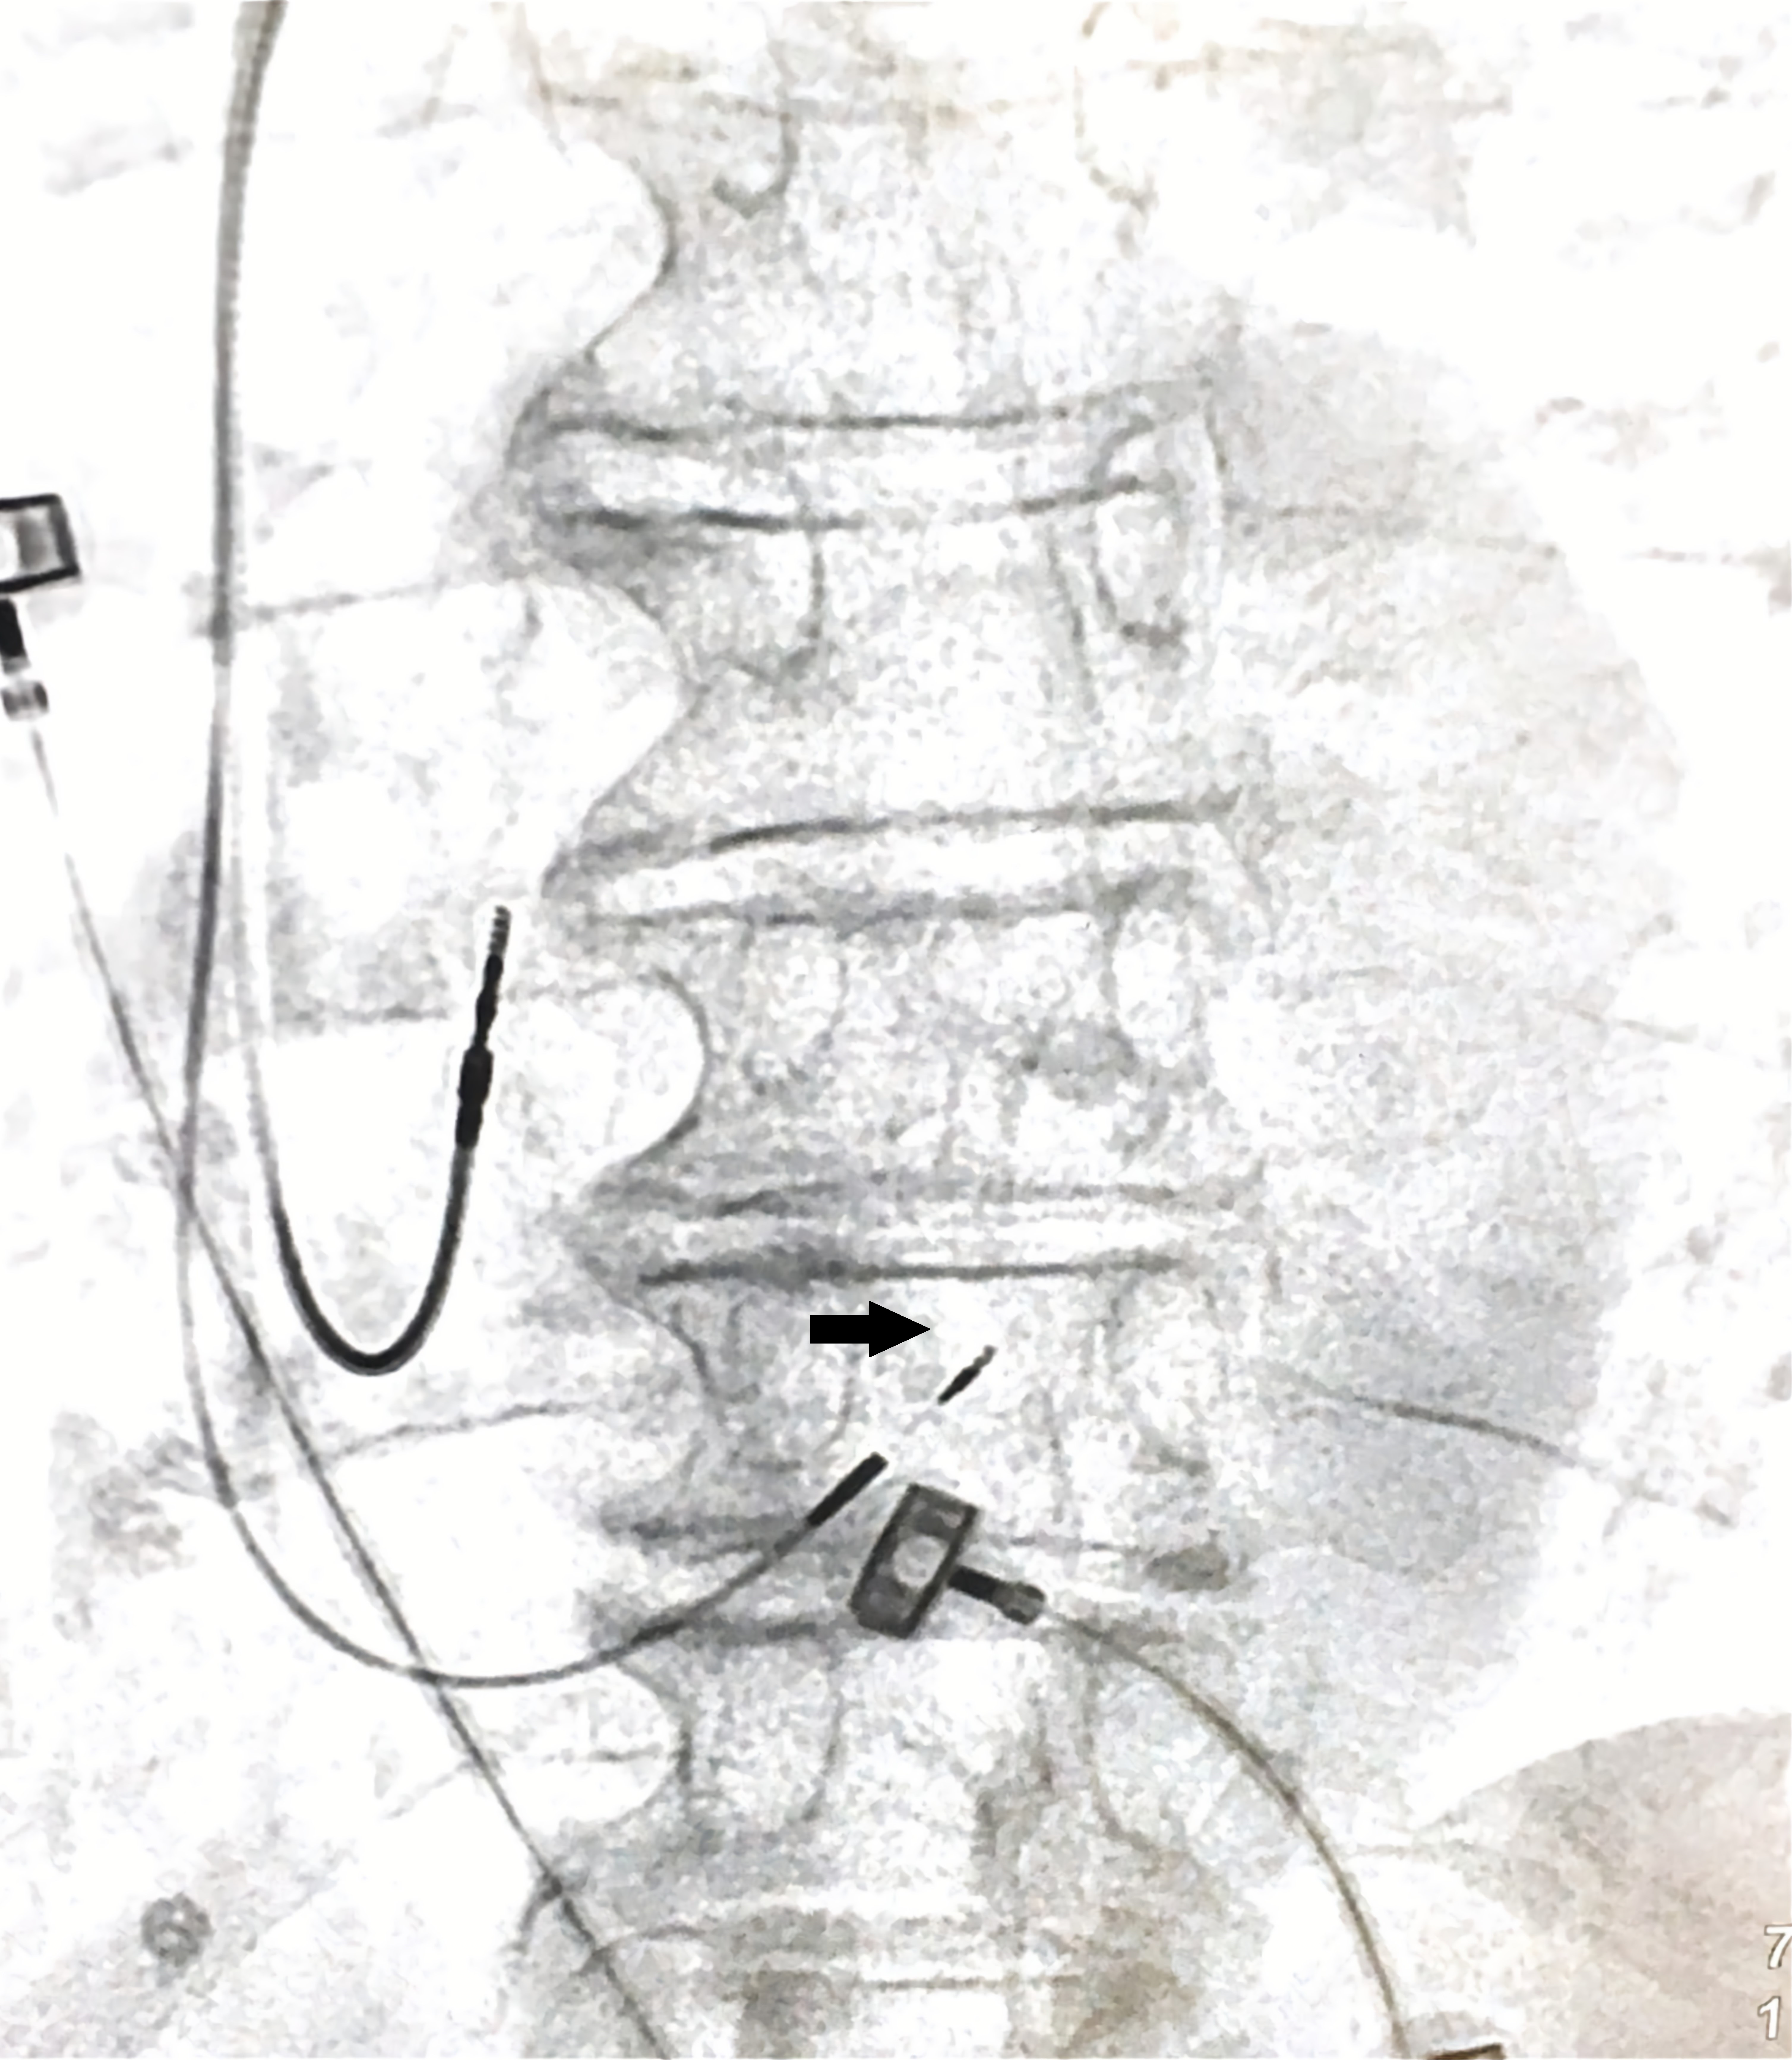

ПГ располагается в мембранозной части межжелу- дочковой перегородки (МЖП), причём проксимальная часть пучка лежит в правопредсердной части перегородки, выше кольца трикуспидального клапана (ТК). Затем ПГ переходит в желудочковую часть перегородки, разделяясь на левую и правую ножки. Выделяют 3 наиболее часто встречающихся варианта расположения ПГ [3]. Тип 1 (46,7% случаев) — ПГ проходит по нижней границе мембранозной части МЖП и прикрыт тонким слоем миокардиальных волокон, простирающихся от мышечной до мембранозной части МЖП. Тип 2 (32,4% случаев) — ПГ проходит в мышечной части МЖП, в стороне от нижней границы мембранозной части. Тип 3 (21,0% случаев) — ПГ не покрыт миокардом и проходит поверх мембранозной части МЖП. Встречаются и более редкие варианты расположения, в т.ч. когда ПГ смещен преимущественно к левой стороне МЖП. ПГ имеет длину 2,3+0,4 мм и ширину '7,3+1,2 мм [4]. Рентгенанатомическая позиция электрода в гисиальной позиции изображена на рисунке 1.

Рис. 1. Рентгенанатомическая проекция электрода в гисиальной позиции. Примечание: черная стрелка указывает на фиксирующую спираль электрода.